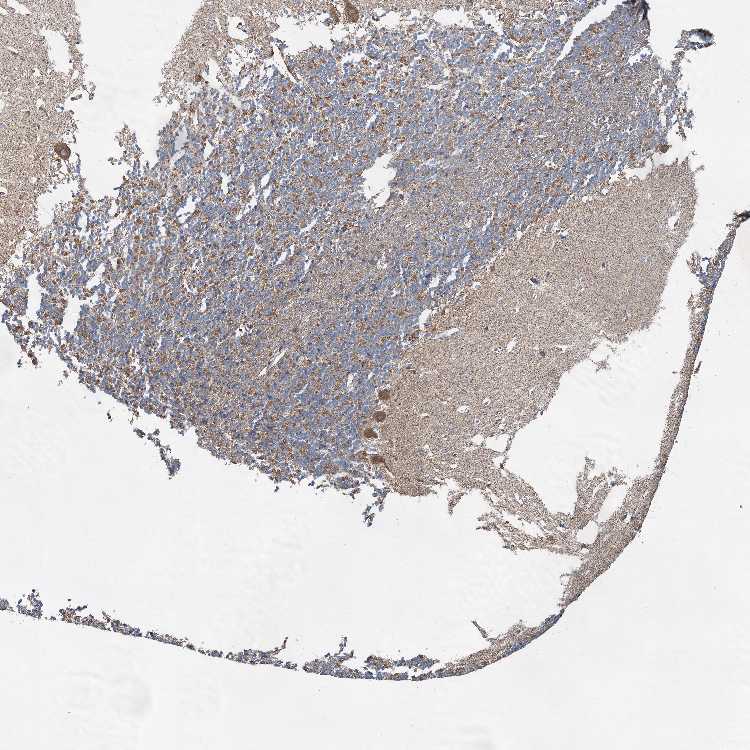

CEREBELLUM - Antibody stainingi

Antibody staining in the annotated cell types in the current human tissue is reported as not detected, low, medium, or high, based on conventional immunohistochemistry profiling in selected tissues. This score is based on the combination of the staining intensity and fraction of stained cells.

Each image is clickable and will lead to virtual microscopy that enables deeper exploration of all samples and also displays staining intensity scores, fraction scores and subcellular localization as well as patient and tissue information for each sample.

Antibody HPA039965

Purkinje cells Medium

Cells in granular layer Medium

Cells in molecular layer Not detected